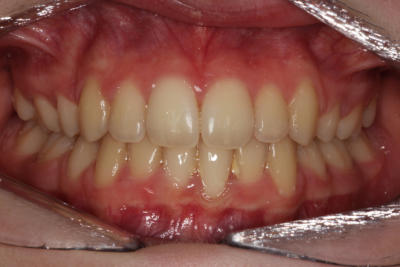

Crowding with lateral open bite – Child case